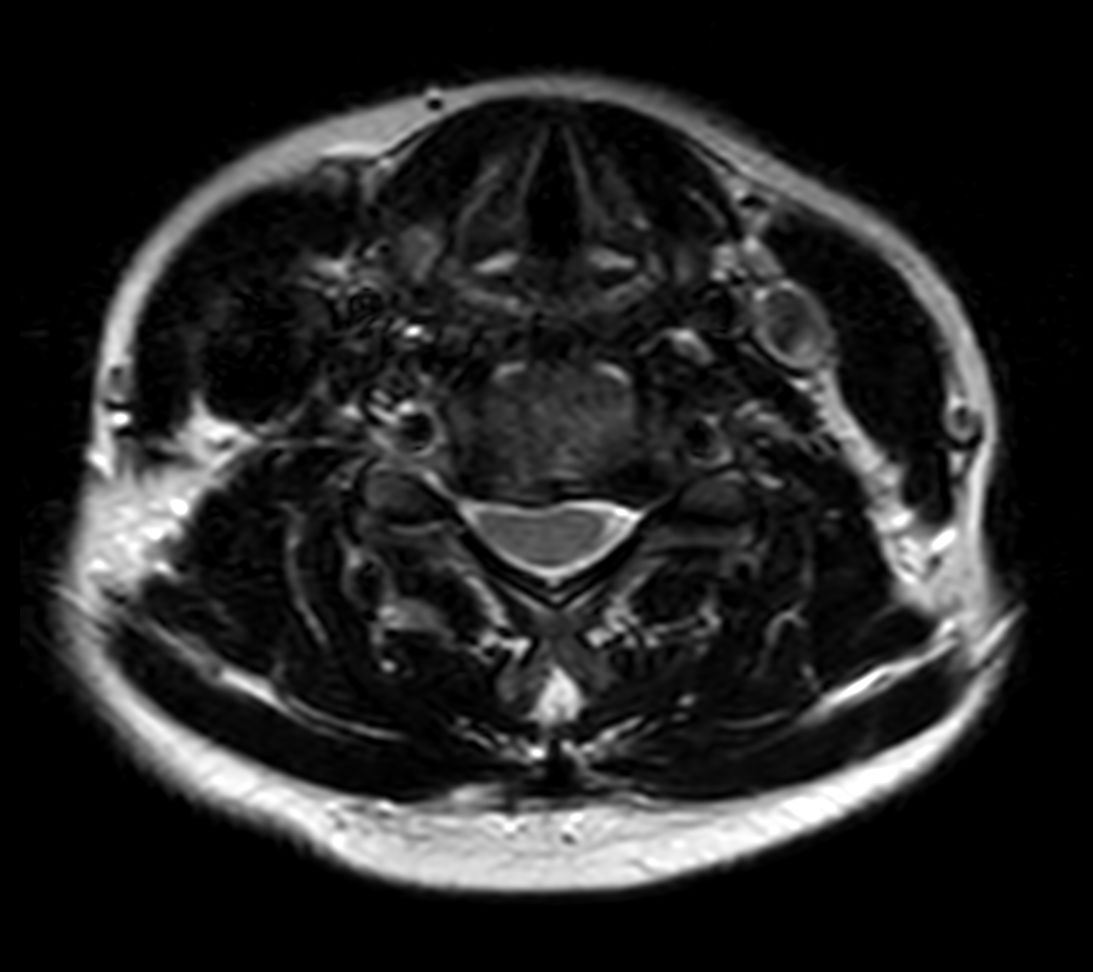

Axial T2w TSE

Axial T2w FFE 3D